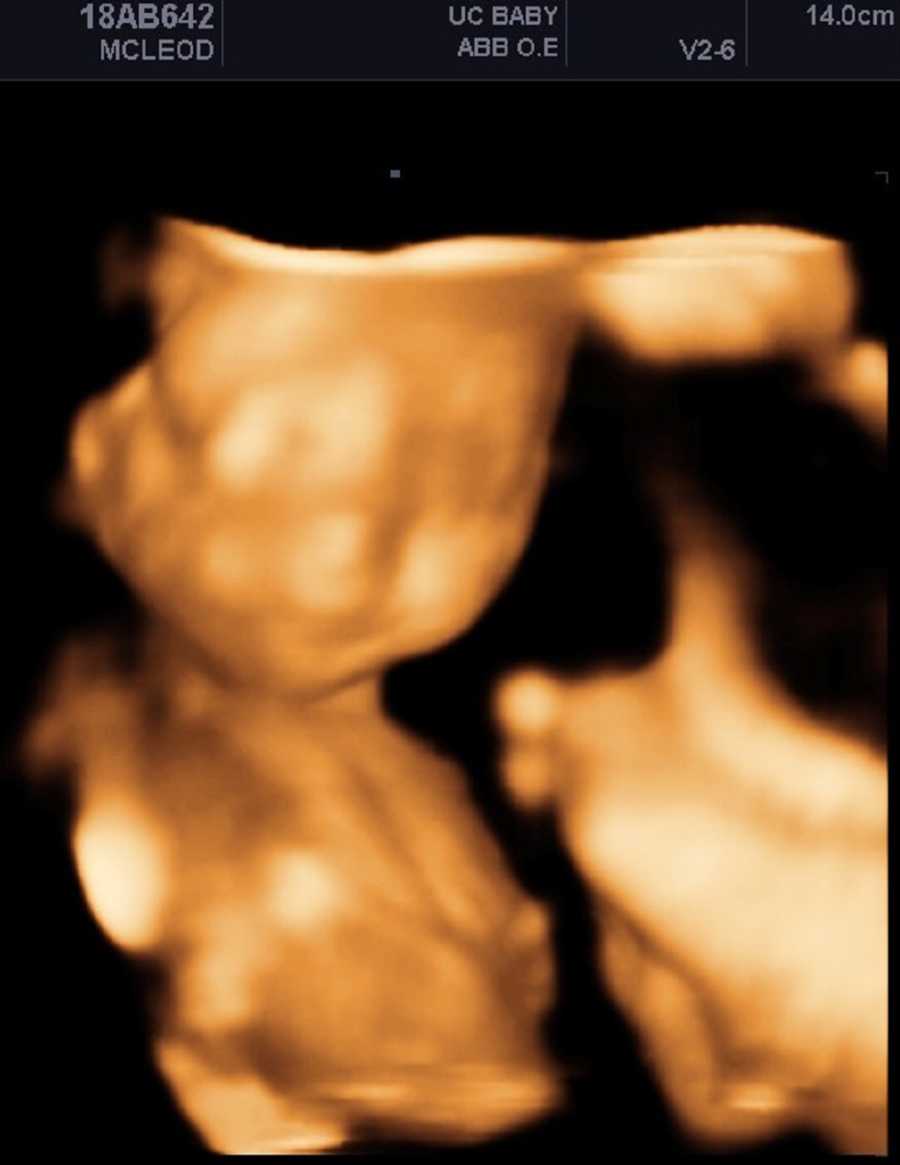

“Ho scoperto le differenze negli arti della mia seconda figlia Ivy a 19 settimane. Mio marito era via per lavoro, quindi mia madre e mia sorella sono venute con me al mio appuntamento con l’ecografia per aiutarmi con l’altra mia figlia piccola e dare un’occhiata al bambino. Ricordo che l’ecografia ha richiesto un’eternità, ma il tecnico mi ha detto che le gambe del bambino erano incrociate e in una posizione difficile per determinare il sesso. Non ci ho pensato. Abbiamo tutti commentato le sue dita dei piedi carine e le foto sono state stampate, e non ci siamo nemmeno accorti che non c’era menzione delle sue mani.”

Il giorno dopo lei e il marito sono andati all’ospedale pediatrico di Vancouver per effettuare un’ecografia dettagliata e incontrare esperti in genetica e perinatologia, non senza aver passato la notte a cercare su internet protesi per bambini e a vedere video di bambini focomelici, iniziando a sentire un briciolo di speranza.